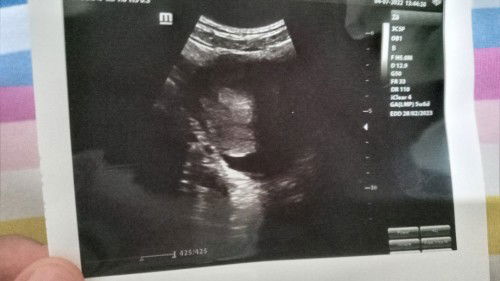

Hamil 6w tapi masih penebalan dinding rahim itu wajar nggak ya bund.

Saya terlat hed 10 hari, Selasa kemarin saya tespek garis dua, pas ke dokter katanya iya hamil tapi usg masih penebalan dinding, dan beberapa hari kemarin saya kram perut, pinggang, sama payudara terasa nyeri ketika di sentuh. Apa itu wajar bun?